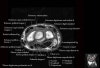

- Sagittal section

Sagittal T1 evaluates the tendons, bone marrow and relationships between the osseous structures.